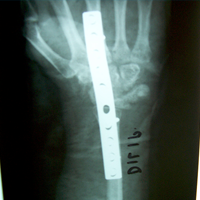

Case:1 GCT L/E Radius

Limb Reconstruction Doctor in Ahmedabad

Pre-Op

Rehablition Doctor In Ahmedabad

One and Half month follow up

Rehablition Best Doctor In India

One and Half year foll

2 years Follow-Up